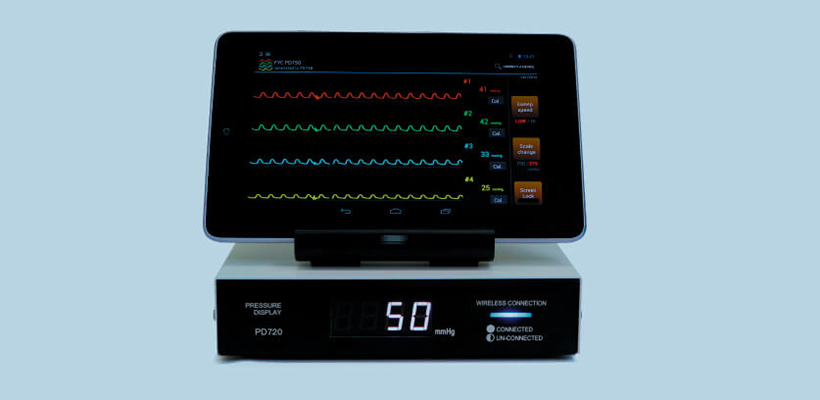

Vascular IVR

Products